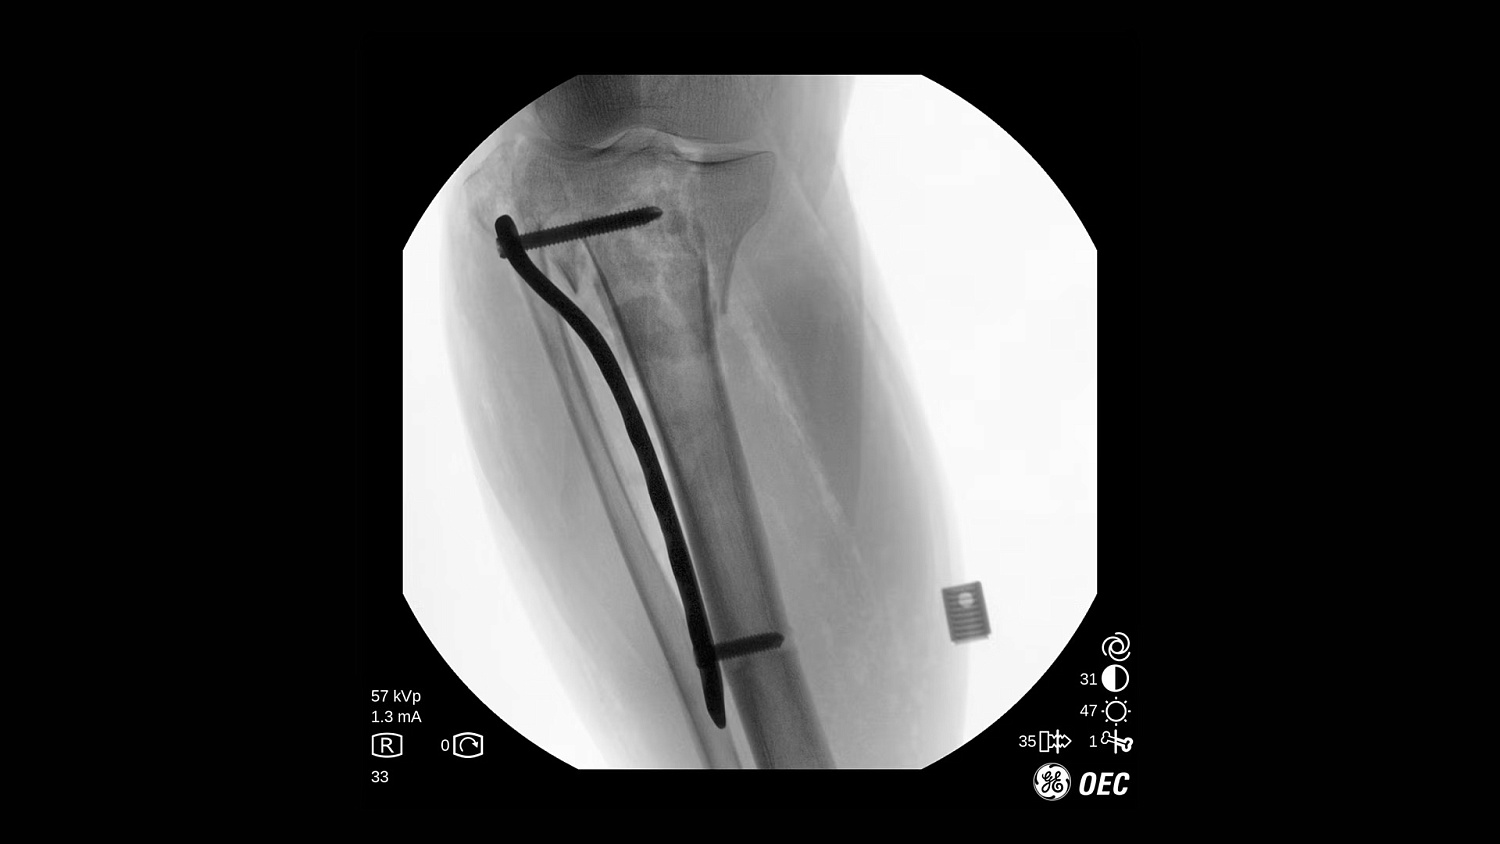

GE Healthcare OEC One CFD относится к классу мобильных рентгеновских аппаратов с С-образной дугой, в которых все ключевые узлы — излучатель, детектор, монитор и панель управления — объединены в единую компактную конструкцию. КМОП-плоскопанельный детектор и фирменная цепочка обработки Clear View обеспечивают высокую детализацию изображения в широком спектре клинических задач: от рутинных травматолого-ортопедических вмешательств до эндоваскулярных процедур и сложной спинальной хирургии. Интеллектуальные алгоритмы подавления помех от металлоконструкций, автоматической оптимизации окна и уровня, а также режимы увеличения позволяют уверенно визуализировать мелкие структуры, проводники и импланты без существенного роста дозовой нагрузки.

- Интеллектуальные алгоритмы обработки изображения (в том числе подавление помех от металлоконструкций и автоматический выбор окна/уровня).

- Функции Live Zoom и работа с последней рентгеноскопической последовательностью для снижения количества повторных экспозиций.

- Режимы рентгеноскопии, цифрового снимка и субтракционной ангиографии для интраоперационного контроля хода вмешательств.

- Специализированные клинические профили для ортопедии, спинальной хирургии, общей хирургии, урологии, сосудистых и болевых процедур.

| Режим цифрового снимка (Digital Spot) | Получение высокодетализированного статического кадра для оценки критически важных анатомических структур. |